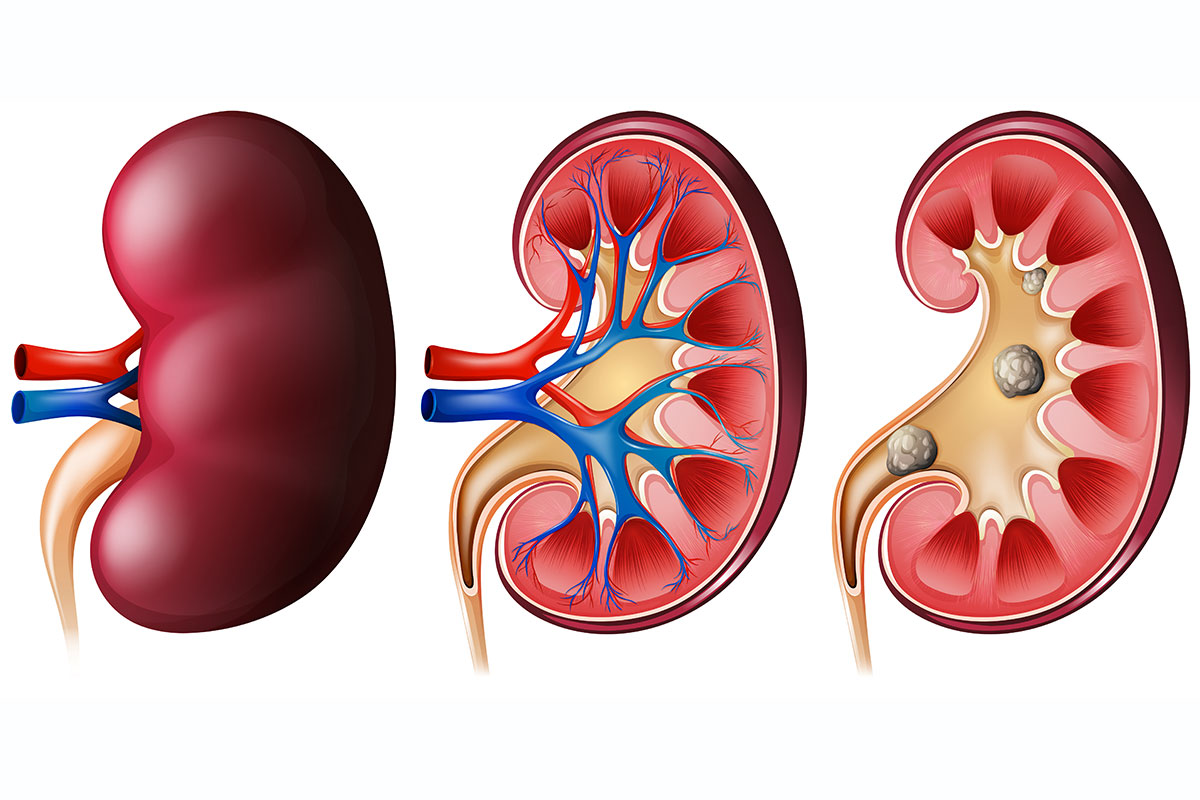

• Renal Stones

Renal Stones or Gall Stones, Nephripih, Protein Urea etc...